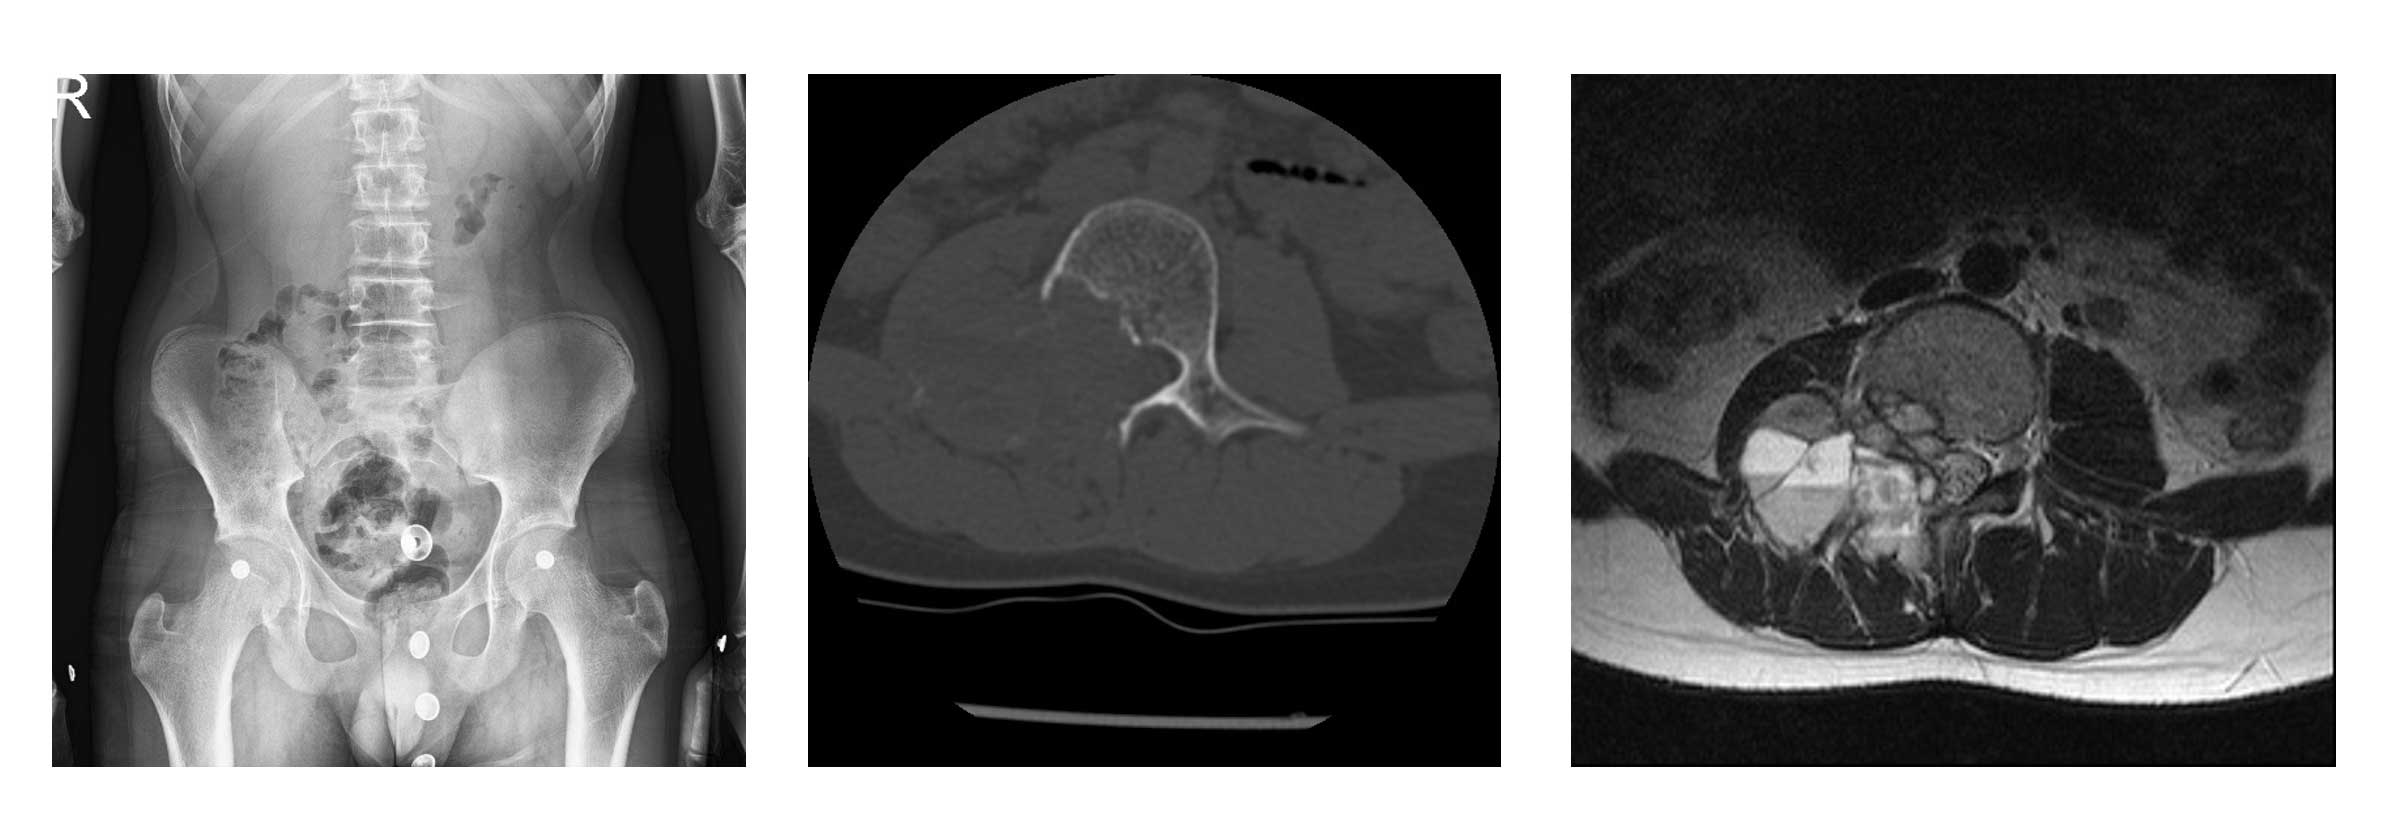

Ameliyat Öncesi: Röntgende L3 vertebra sağ pedikülde harabiyet, tomografide kemik yıkımı ve MR’da sıvı sıvı seviyesi görülmekte.